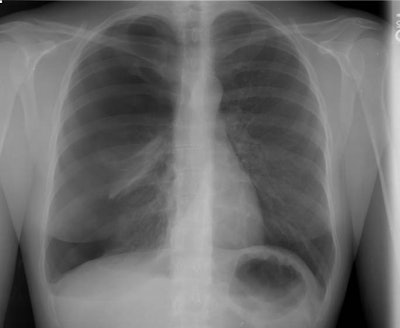

Right Pneumothorax

The female patient shown below presented with shortness of breath and right sided pleuritic chest pain. The chest radiograph demonstrated a large right pneumothorax with compressive atelectasis of the right lung. Despite chest tube placement, the pneumothorax persistent and the patient required thoracoscopic surgery for apical blebs.